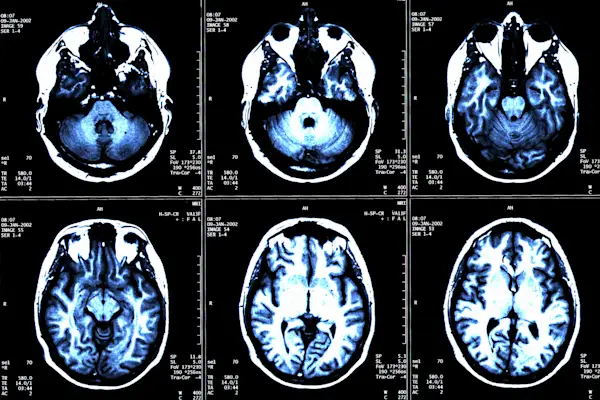

关于MS脑病变的6件事

他们是什么,如果可以防止,为什么治疗如此重要。